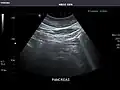

Abdominal Ultrasound (Full Exam)

STRUCTURED REPORT

(Technique: Transabdominal ultrasonography; Device: Toshiba Aplio XG)

Pancreas: Visualized portions unremarkable.

Pancreas -